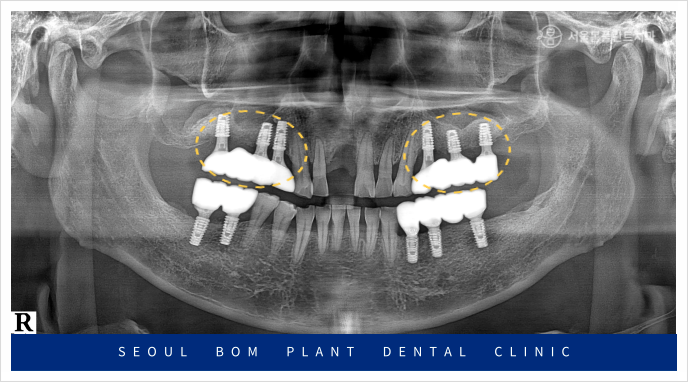

양측 위아래 어금니의

임플란트 보철물이 마무리되고 나서

앞니 심미보철치료를 진행하였는데요.

앞니는 심미성이 중요한

부위이다 보니 치아를 다듬기 전

환자분과 함께 색상과 모양을

꼼꼼하게 확인하는 작업을 거쳤으며

보철물 수복에

필요한 만큼의 양만 삭제하여

신경치료 없이 진행을 하였습니다.

앞니도 어금니와 마찬가지로

심미성이 높은 지르코니아

보철물로 수복해 드리면서

모든 치료를 마무리해 드렸는데요.

환자분께서는 임플란트를

사용하실 때보다

훨씬 더 심미적여서

마음에 드신다고 말씀해 주셨으며,

양측 어금니의 식사가 가능해져

만족해 하셨는데요.